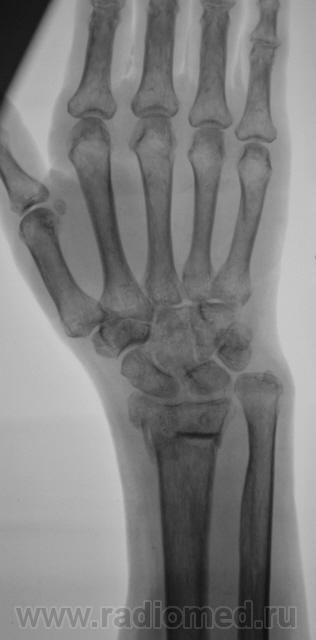

Фрагменты с увеличением.

Пусть интересуется... Гипс снят рановато, стояние отломков - неудовлетворительно,хотя бывает и хуже

Если срок сращения 4 недели, то признаки консолидации выражены соответственно сроку достаточно хорошо. Перелом компрессионный, поэтому произошел вывих в л/л суставе. Можно или нет его было устранить в амбулаторных условиях - судить не берусь. Осколок кортикала в луче "захряснет", может, рассосется - ничего страшного.

неприятная ситуация(особенно если не было первичной репозиции) есть оппределенные правила ведения таких переломов, первичный снимок, сразу после репозиции, через 4-5 дней после репозиции и если нет вторичного смещения в гипсе то через 4-5 недель уже без гипса. ситуация на данный момент спорная, лучше наложить аппарат Илизарова для дальнейшей иммобилизации и профилактики контрактуры л\зап сустава. если возраст пациентки почтенный, то гипсовая иммобилизация доолжна быть продлена до 8 недель.